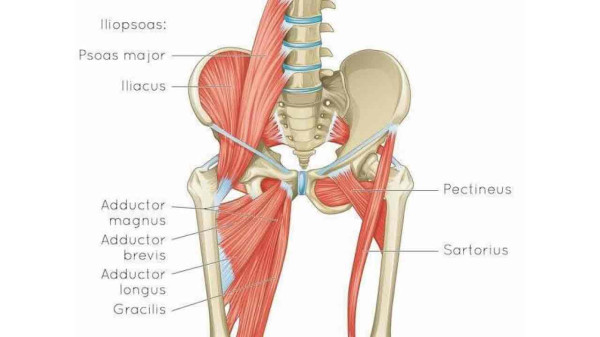

Анатомия и Функции Мышцы Adductor Magnus